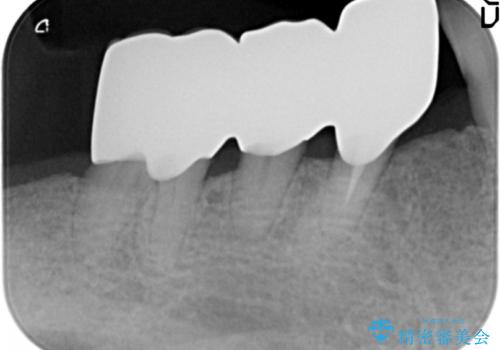

骨を再生させて歯周病を治す 再生療法 50代男性

- 全顎的な重度歯周病の患者様です。

骨吸収の進行している右下臼歯部に、再生療法(骨を増やす手術))を行いました。

再生療法から1年後、リエントリー手術により骨の再生を確認し、骨外科処置(骨を平らにして歯周ポケットの根本的な改善を図る処置)を行いました。

被せ物の種類:オールセラミッククラウン ベレッツァ

再生療法と骨外科処置により、歯周ポケットは全周2mm以下となりました。

根本的な歯周病の治療を行うことで不安がなくなり、患者様に喜んで頂けました。

奥歯の動揺がなくなりしっかりと咬むことができ、審美的・機能的にもご満足頂けました。